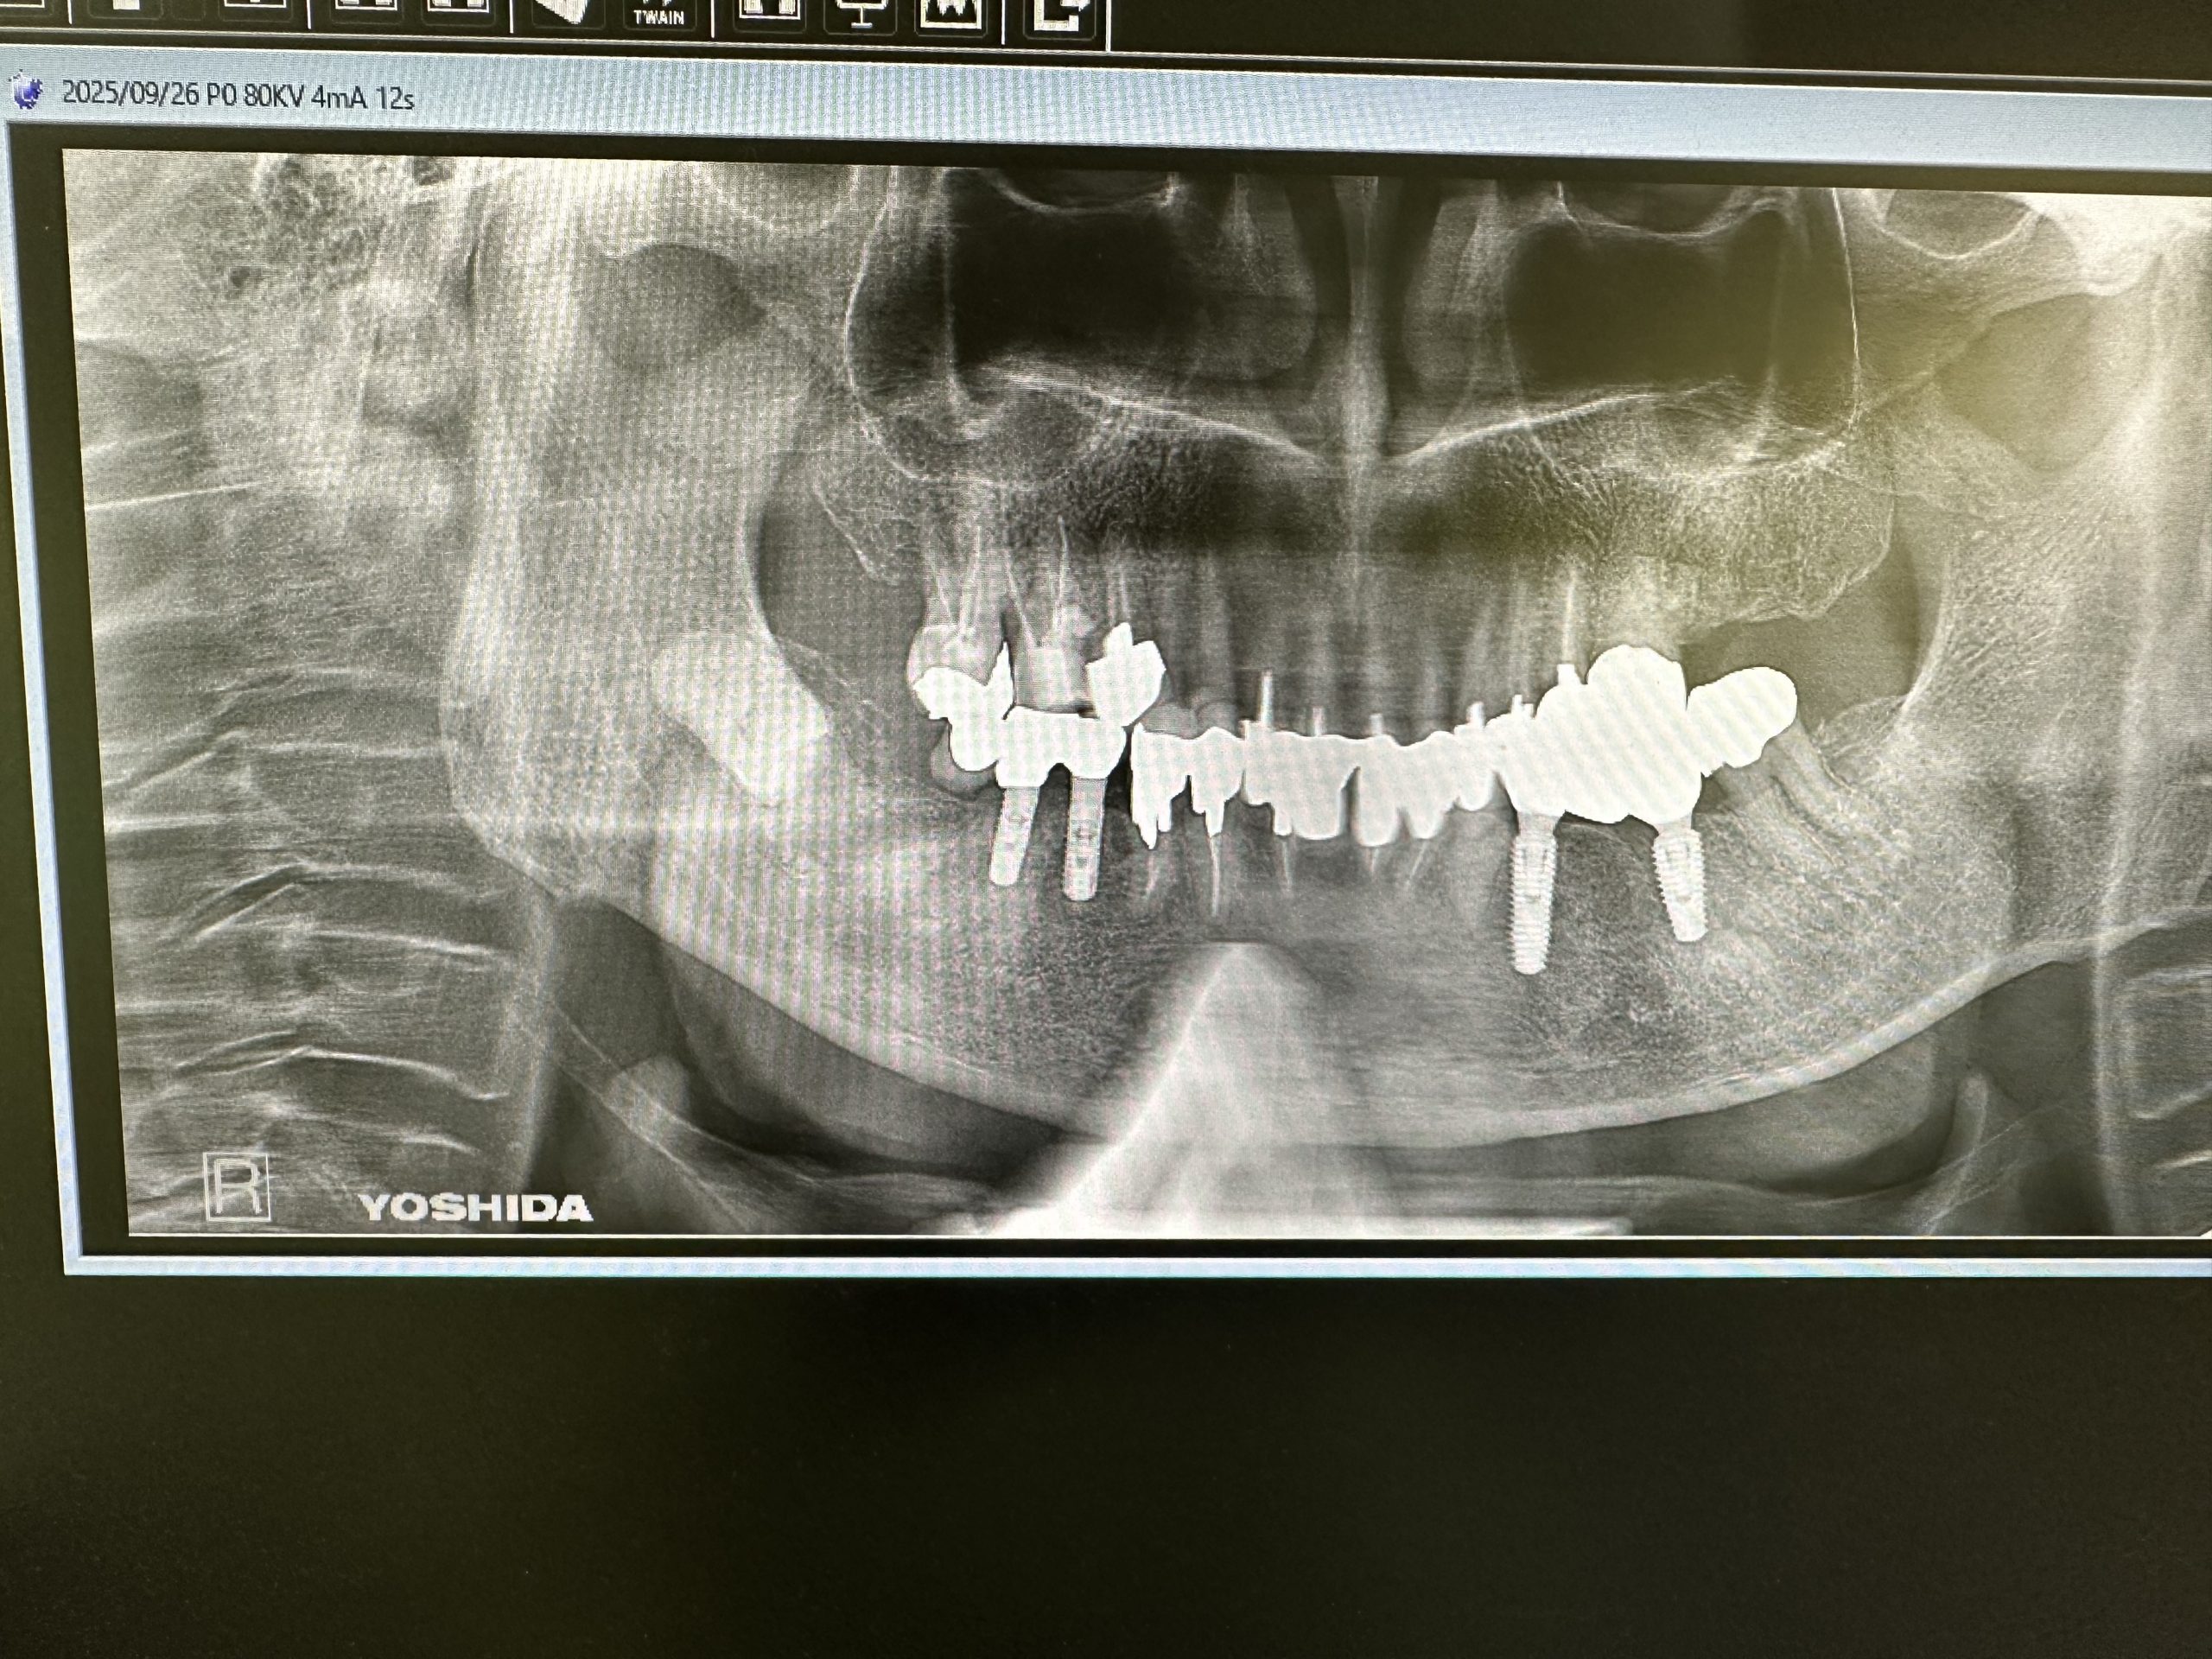

今日は2件インプラントブリッジセット

ほぼ2か月で終了

上下問わず、オペ時、計測値が良い場合は6w後再計測し著しい下降なくI SQ70以上であれば印象しています

画像からも歯肉緣からプラットフォームまでの4ミリルールが守られており良い絵面だ🤪